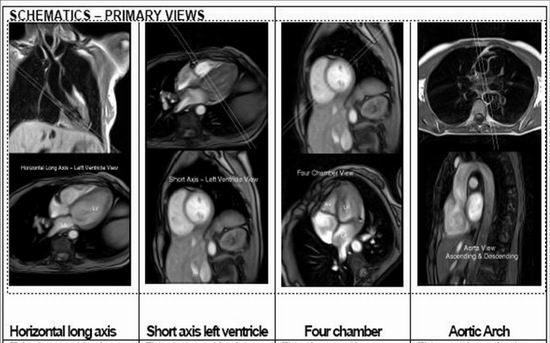

名称:1.5磁共振成像系统

主要功能:Avanto 1.5T磁共振成系统整体提升至I-class平台,将品质图像、高工作效率、高灵活度的工作完美结合在一起,而Tim(Total imagingmatrix)则是一次革命性突破。它带来的全新的极具创造性的射频系统和矩阵线圈使之成为划时代磁共振影像技术的一大亮点,并可实现从头到脚的快速扫描,优异的图像质量能为医生和患者朋友提供强大的技术支持。